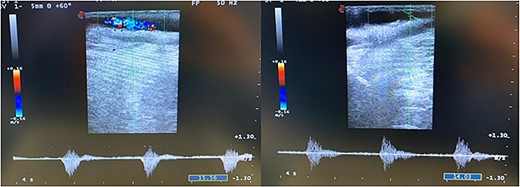

Duplex ultrasound examination (DUS, Fig. 1) showed a segmental sub-occlusive hypoechoic stenosis of the anterior wall of the right CFA.

The intraoperative completion DUS showed the patency of the CFA and of the femoro-popliteal axis with triphasic flow maintained until tibial vessels (Fig. 4).